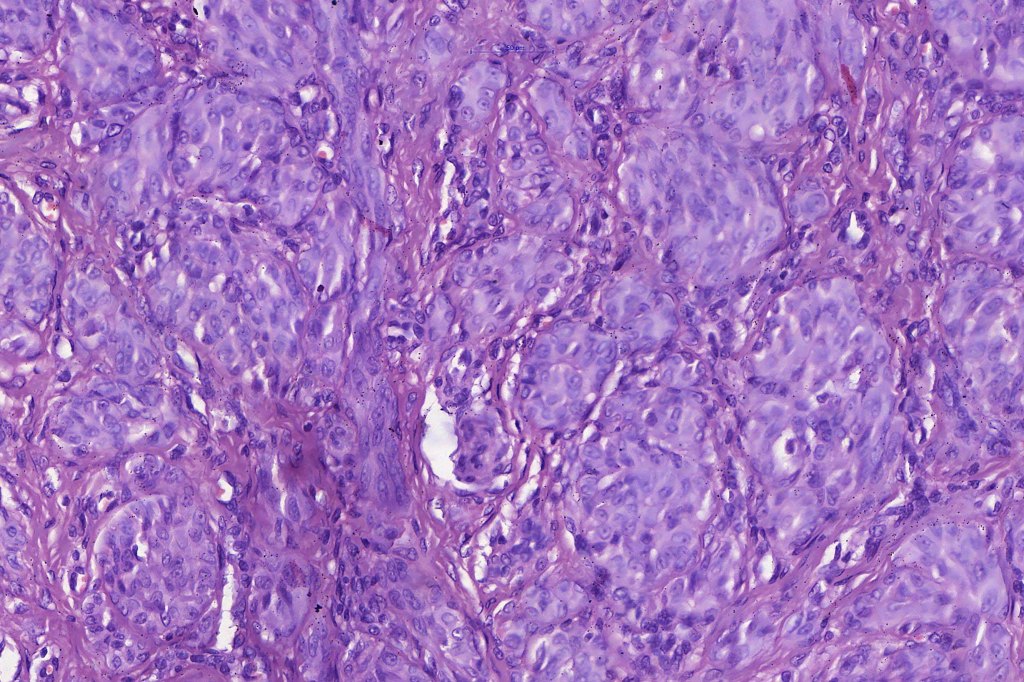

•Spindle cells have abundant cytoplasm and vesicular nuclei with small nucleoli

•Epithelioid cell variants often show greater pleomorphism and cells can frequently appear bizarre with abundant, sometimes ground glass cytoplasm and large vesicular nuclei with prominent eosinophilic nucleoli, multinucleate cells are often seen

•Intracytoplasmic pseudoinclusions commonly present in epithelioid cells

•Mitoses can brisk in younger patients and should not be taken as indicating melanoma

•Mitoses are restricted to the superficial aspect on the nevus and are never atypical